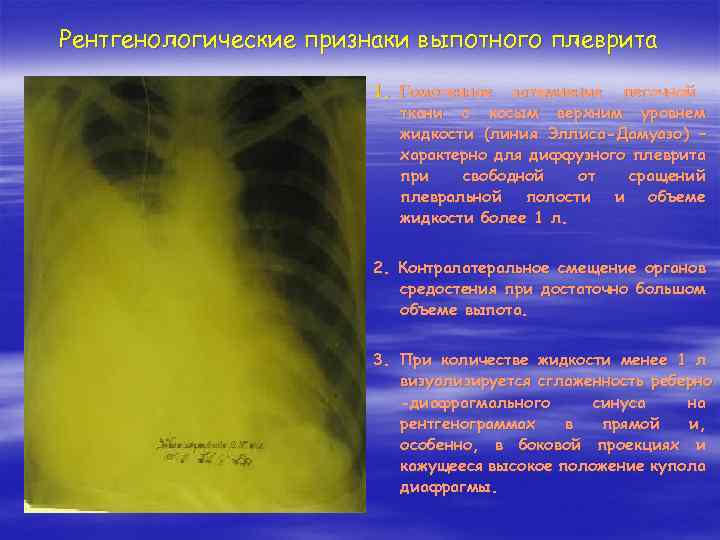

Диагностика плеврального выпота: что нужно знать